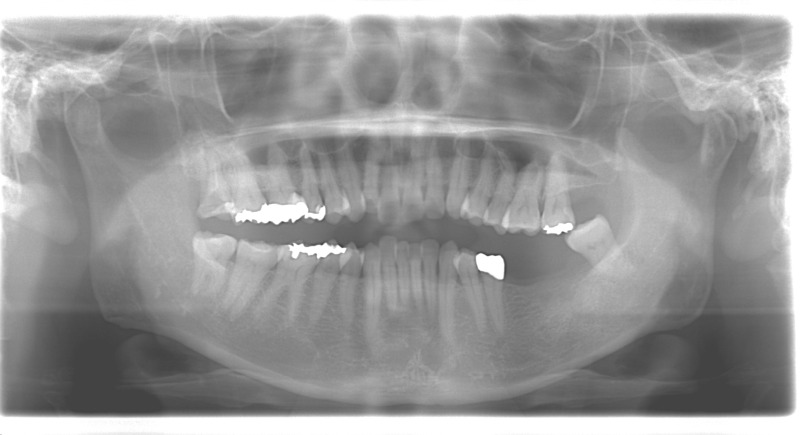

症例

50代女性のインプラント治療

担当医の処置方針

左下2本の欠損部にはインプラント治療を行いました。 矯正も希望されていたので、インプラントと矯正治療を同時に進めました。 また、不良補綴の再製も行い、理想の咬合平面となりました。

Before

Before